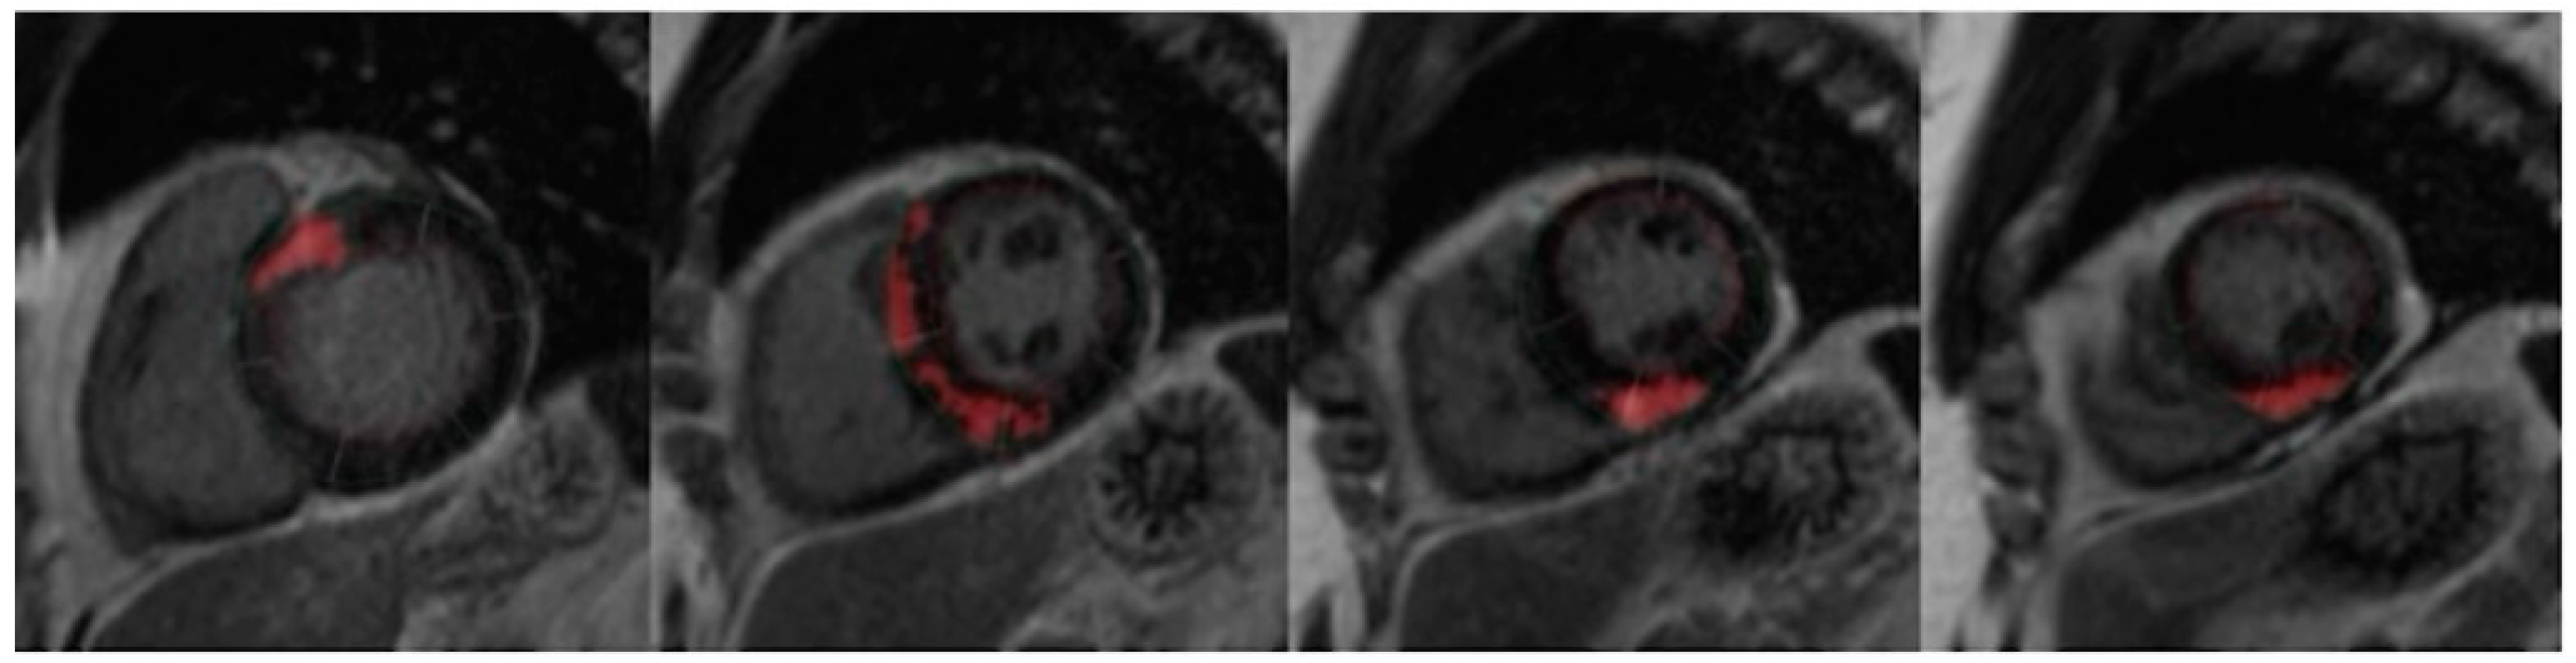

4. Cardiac MRI

6.1. Correlation of LVWT and LVMI with LV Fibrosis

6.2. Predictors of VT